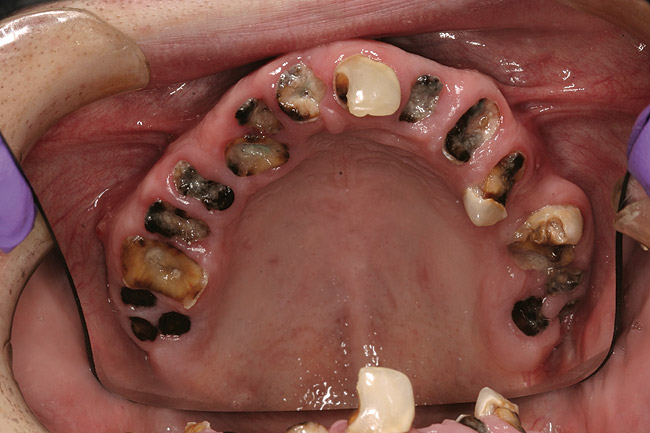

When smoked, methamphetamine produces highly toxic and corrosive fumes of lithium, muriatic, and sulfuric acids that can destroy enamel rapidly. With continued use, methamphetamine can produce severe, rampant caries, similar to early childhood caries. Patients have reported noticing changes in the appearance of tooth structure in as little as 3 months of use. The affected surfaces are the buccal and labial smooth surfaces, as well as the interproximal surfaces (Figure 1 through Figure 3). Because in the general population the vast majority of decay is found in the posterior molars, when someone presents with rampant anterior lesions it should be a red flag for methamphetamine use.5

Figure 3  DEVASTATING EFFECTS When smoked, methamphetamine produces highly toxic and corrosive fumes of lithium, muriatic, and sulfuric acids that can destroy enamel rapidly. With continued use, methamphetamine can produce severe, rampant caries. When someone presents with rampant anterior lesions it should be a red flag for methamphetamine use.

Figure 3